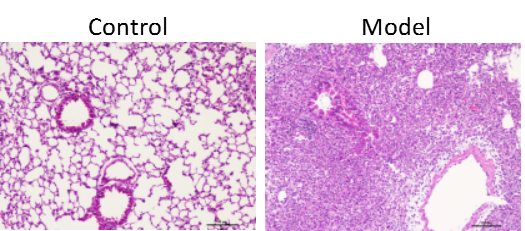

2.1HE检测